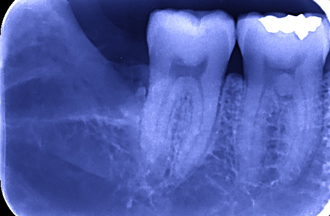

レントゲンで確認すると、親知らずの歯は、真横向き=写真=に生えていました。私は「この抜歯は今すぐには…」と考え、日を改めて抜歯をさせて頂くことになりました。

別の日、患者様の頑張りもあって、抜歯はスムーズに終わりました。抜歯後は、当院のパターン